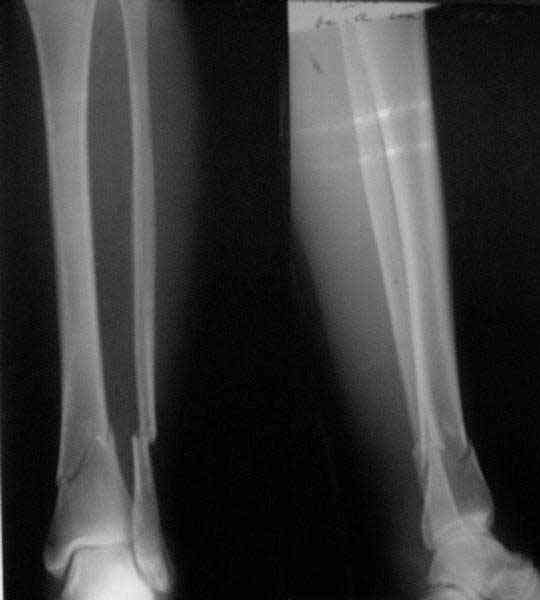

A typical case is attached, also an image with intra-op reduction obtained by a small wire distractor, in the moment of insertion a Poller wire in AP direction. Fixation by a SIGN nail. Despite the fibula was not fixed healing was obtained with the unchanged alignment.

Very interesting application, but is the final position in a little distal varus with some fibula

distraction? Would that have been eliminated by fibula plating?

At least both the ankle mortise and tibial alignment look acceptable, don't they?

I am just trying to illustrate that prevention of 1)tibial valgus and 2)loss of reduction can be provided without fibular plating. Small changes of conventional nailing techniques allow to maintain reduction of the tibia reliably without adjunctive fibular stabilization.

In delayed cases acute length restoration performed only in the tibia may leave the fibula shortened thus change the mortise. So it is reasonable to restore length of both bones simultaneously by distractor and fix the fibula not with open reduction and plating but just by a single perQ screw. Example attached.